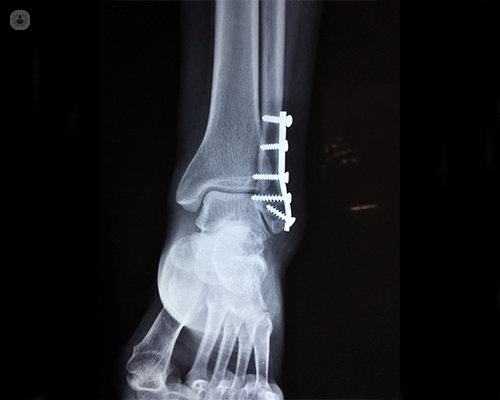

Complex Trauma Surgeries

Fractures and traumatic injuries happen unexpectedly. And while there's no way to prepare for such an injury, it's comforting to know you are in experienced hands. Our experienced surgeons are expert in handling Orthopaedic Trauma situations and perform minimally invasive surgery.

Trauma surgery is a surgical specialty which deals in trauma or accident related surgeries. It requires years of training in trauma surgery and critical care. Trauma surgeons are first required to stabilize the patient and then evaluating and managing the conditions of the patient. In our hospital, we have a trauma team which consist of health care professionals from all cadres like Orthopaedic Trauma Surgeon, General Surgeon, Neurosurgeon, Plastic Surgeon including nurses and support staff who understand that the needs of the trauma patients are very different from a planned surgery patient.

How are complex trauma fractures treated?

The management of fractures has improved considerably with excellent outcomes over the last few decades. These excellent outcomes can be obtained through early intervention by staying relatively active whilst keeping the fractured segment immobilised and subsequent rehabilitation to increase strength and range of motion.

Bespoke rehabilitation for each fracture based on patient and fracture characteristics are crucial for optimising the outcomes and to restore previous pre-injury levels. A collaborative multidisciplinary team (MDT) approach led by surgeons, anaesthetists, physiotherapist, occupational therapists, pain specialists, and patients themselves will ultimately lead to return to pre-injury activities of daily living, leisure, sport, and work.

May surgery be required to heal these complex injuries?

Orthopaedic injuries place the patient at risk for various complications, including fat embolism, pneumonia, deep vein thrombosis, and sepsis. Many studies have documented the benefits of early stabilization in reducing morbidity and mortality. Early definitive long bone fixation and external fixation methods have evolved and are considered an integral part of the initial care.

Innovative techniques like computer-assisted surgery continues to develop as technology improves. Uses in trauma include navigation for percutaneous screw placement in trauma surgery and for replacement surgery for reconstruction of complex fractures.

The ultimate target is to enable patients to return to their pre-injury levels. Surgery might be the only option in many of the complex trauma presentations. All these patients should be managed in a collaborative manner. Better understanding and identification of these injuries enables us to optimise the outcomes.